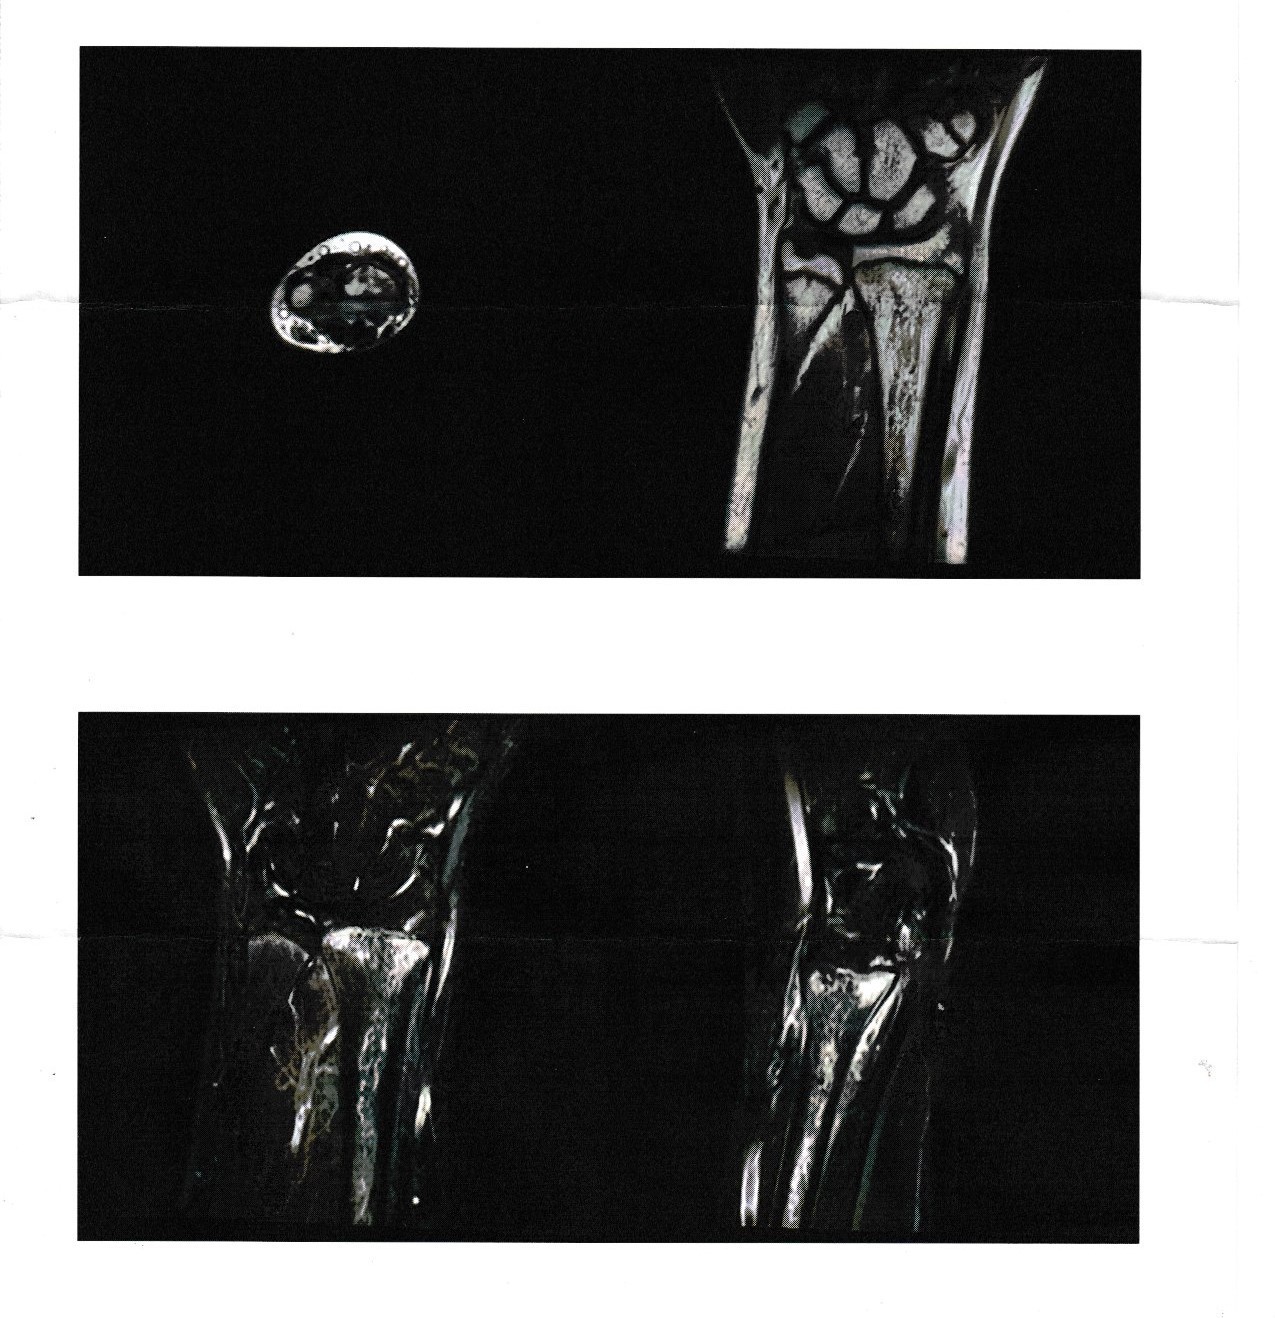

レントゲン画像

MRI画像

レントゲン・MRI画像上、左橈骨遠位端部の骨折ありと診断。

整形外科にて前腕〜手部のギプス固定を施行。